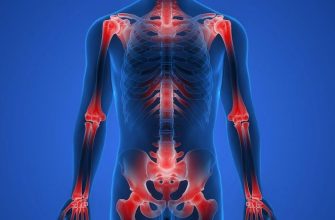

Joint hypermobility, also known as hypermobility syndrome

Joint immobility, also known as stiff joints or limited

Joint pain can be a debilitating condition that affects

Joint pain and swelling can be debilitating, causing

Joint pain is a common ailment that affects millions

Joint and muscle aches can be a common occurrence in

Joint pain and stiffness can be incredibly frustrating

Joint stiffness and pain can be incredibly debilitating